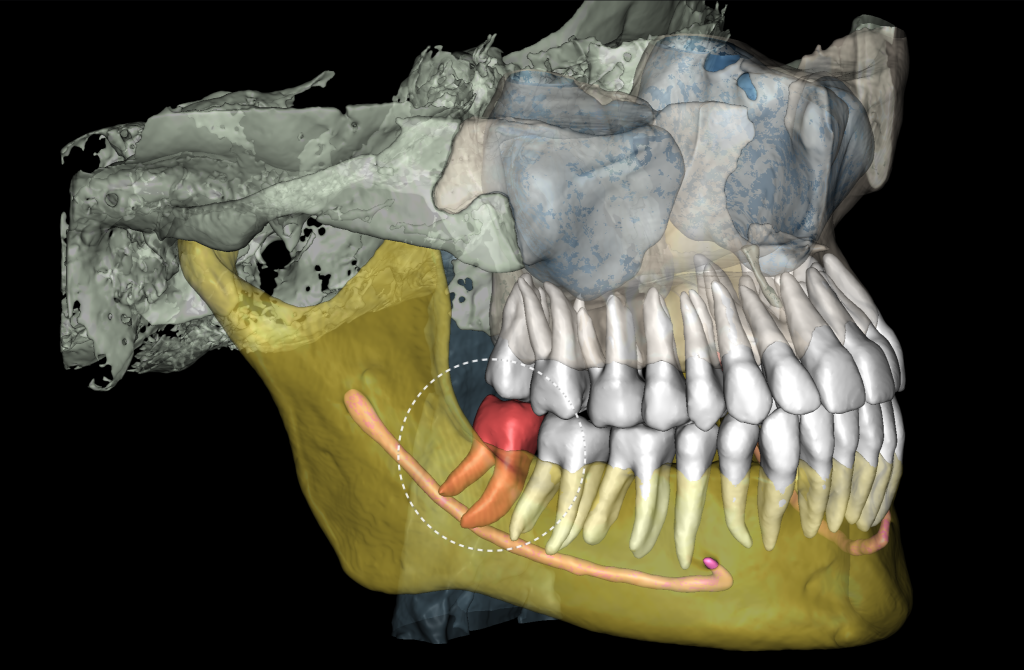

The 3D reconstruction from CBCT data (STL report Diagnocat) is a convenient tool for determining the level of complexity of the upcoming surgical procedure

It also serves as a visualization tool during communication with the patient

“Third Molar Report” created by Diagnocat AI, is a tool which provides accurate tracing of the mandibular canal

And creating an optimal 3D visualization which helps the clinician to determine the distance to the mandibular canal